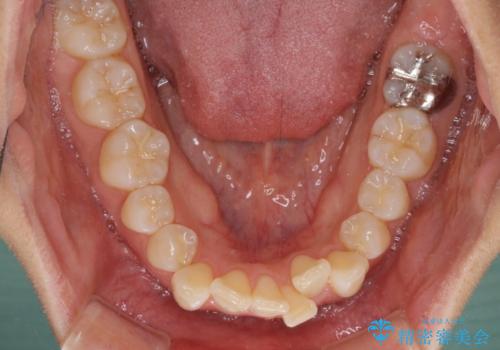

前歯のデコボコを抜歯矯正で改善 メタル装置で費用を抑える

- 前歯のデコボコと口元の突出感を気にして来院された患者様です。

非抜歯矯正ではデコボコを解消することでより口元が突出してしまうため、上下左右の小臼歯4本の抜歯を行い、ワイヤー装置による矯正治療を行うこととしました。